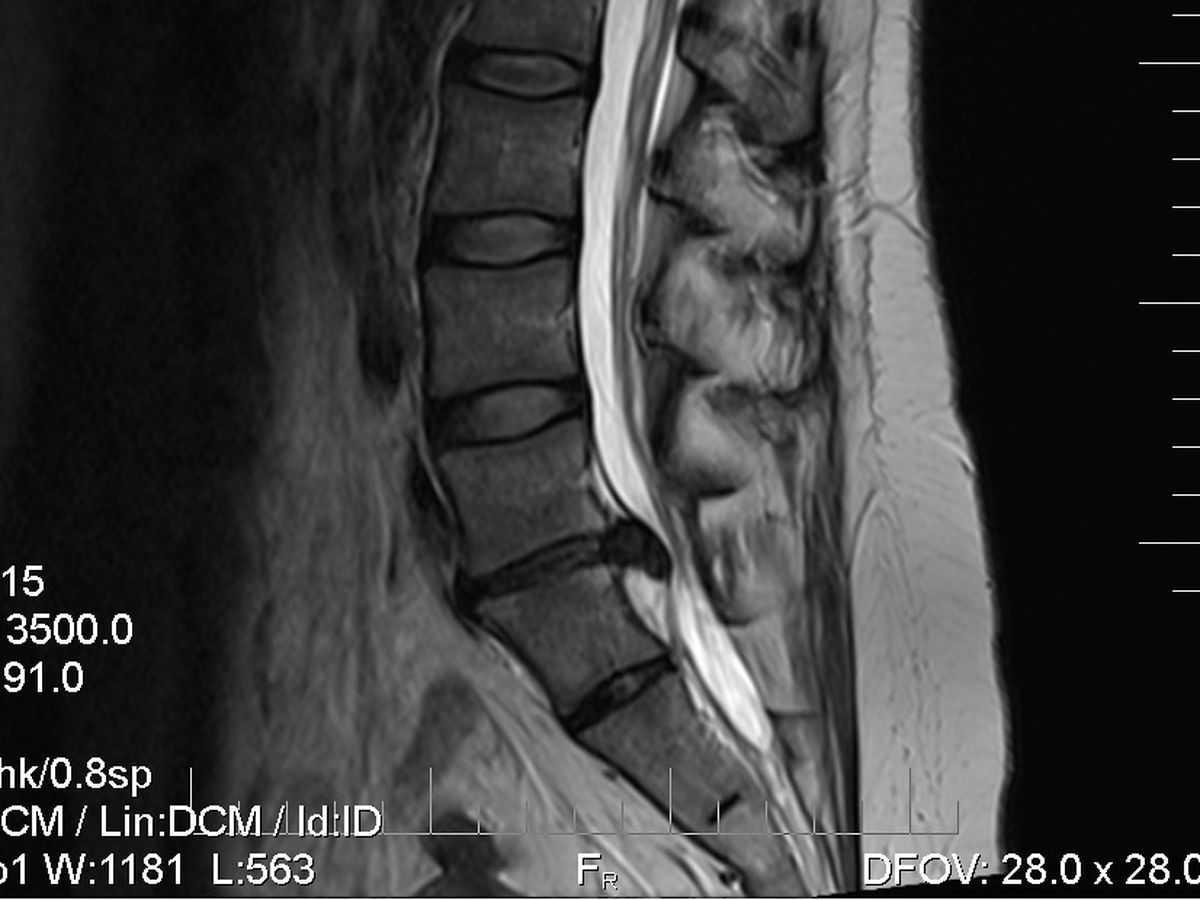

Without physical therapy or any other sort of intervention, I could potentially lose the use of my sciatic nerve causing paralysis in my left leg. Therefore some sort of treatment, whether it be physical therapy or surgery, is required immediately to prevent further injury to the pinched nerve root. As you can see from the MRI, it is not in good shape.